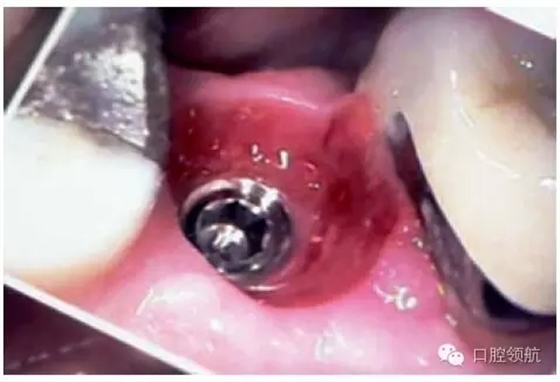

另外一個方面,深的袖口將妨礙修復(fù)體完全就位(圖9.26)。通常可以通過放射學(xué)檢查,確認(rèn)修復(fù)部件的就位情況,包括種植體與基臺的連接部分。即使是內(nèi)連接,轉(zhuǎn)移體或者其他修復(fù)部件也會因深袖口而不能就位。以下技術(shù)可以用于解決這些問題:可以在局部麻醉下,插入喇叭狀或者外展的基臺,以非手術(shù)的方式擴大袖口(圖9.27 a,b),然后再通過放射學(xué)檢查確定部件的完全就位。組織會受壓發(fā)白,15分鐘后,軟組織將會擴張,以允許理想修復(fù)部件的就位,這樣治療將得以繼續(xù)。有時,需要在鄰面做兩個小切口,以緩解袖口軟組織張力(圖9.28 a,b)。通常不需要縫合。一旦袖口組織塑形完成,可運用最佳塑形的臨時(圖9.29)或最終部件(圖9.30),來維持理想的軟組織外形。

圖9.29 由于使用臨時冠成形,上頜第二前磨牙區(qū)域,組織袖口形態(tài)(卵圓形)良好。